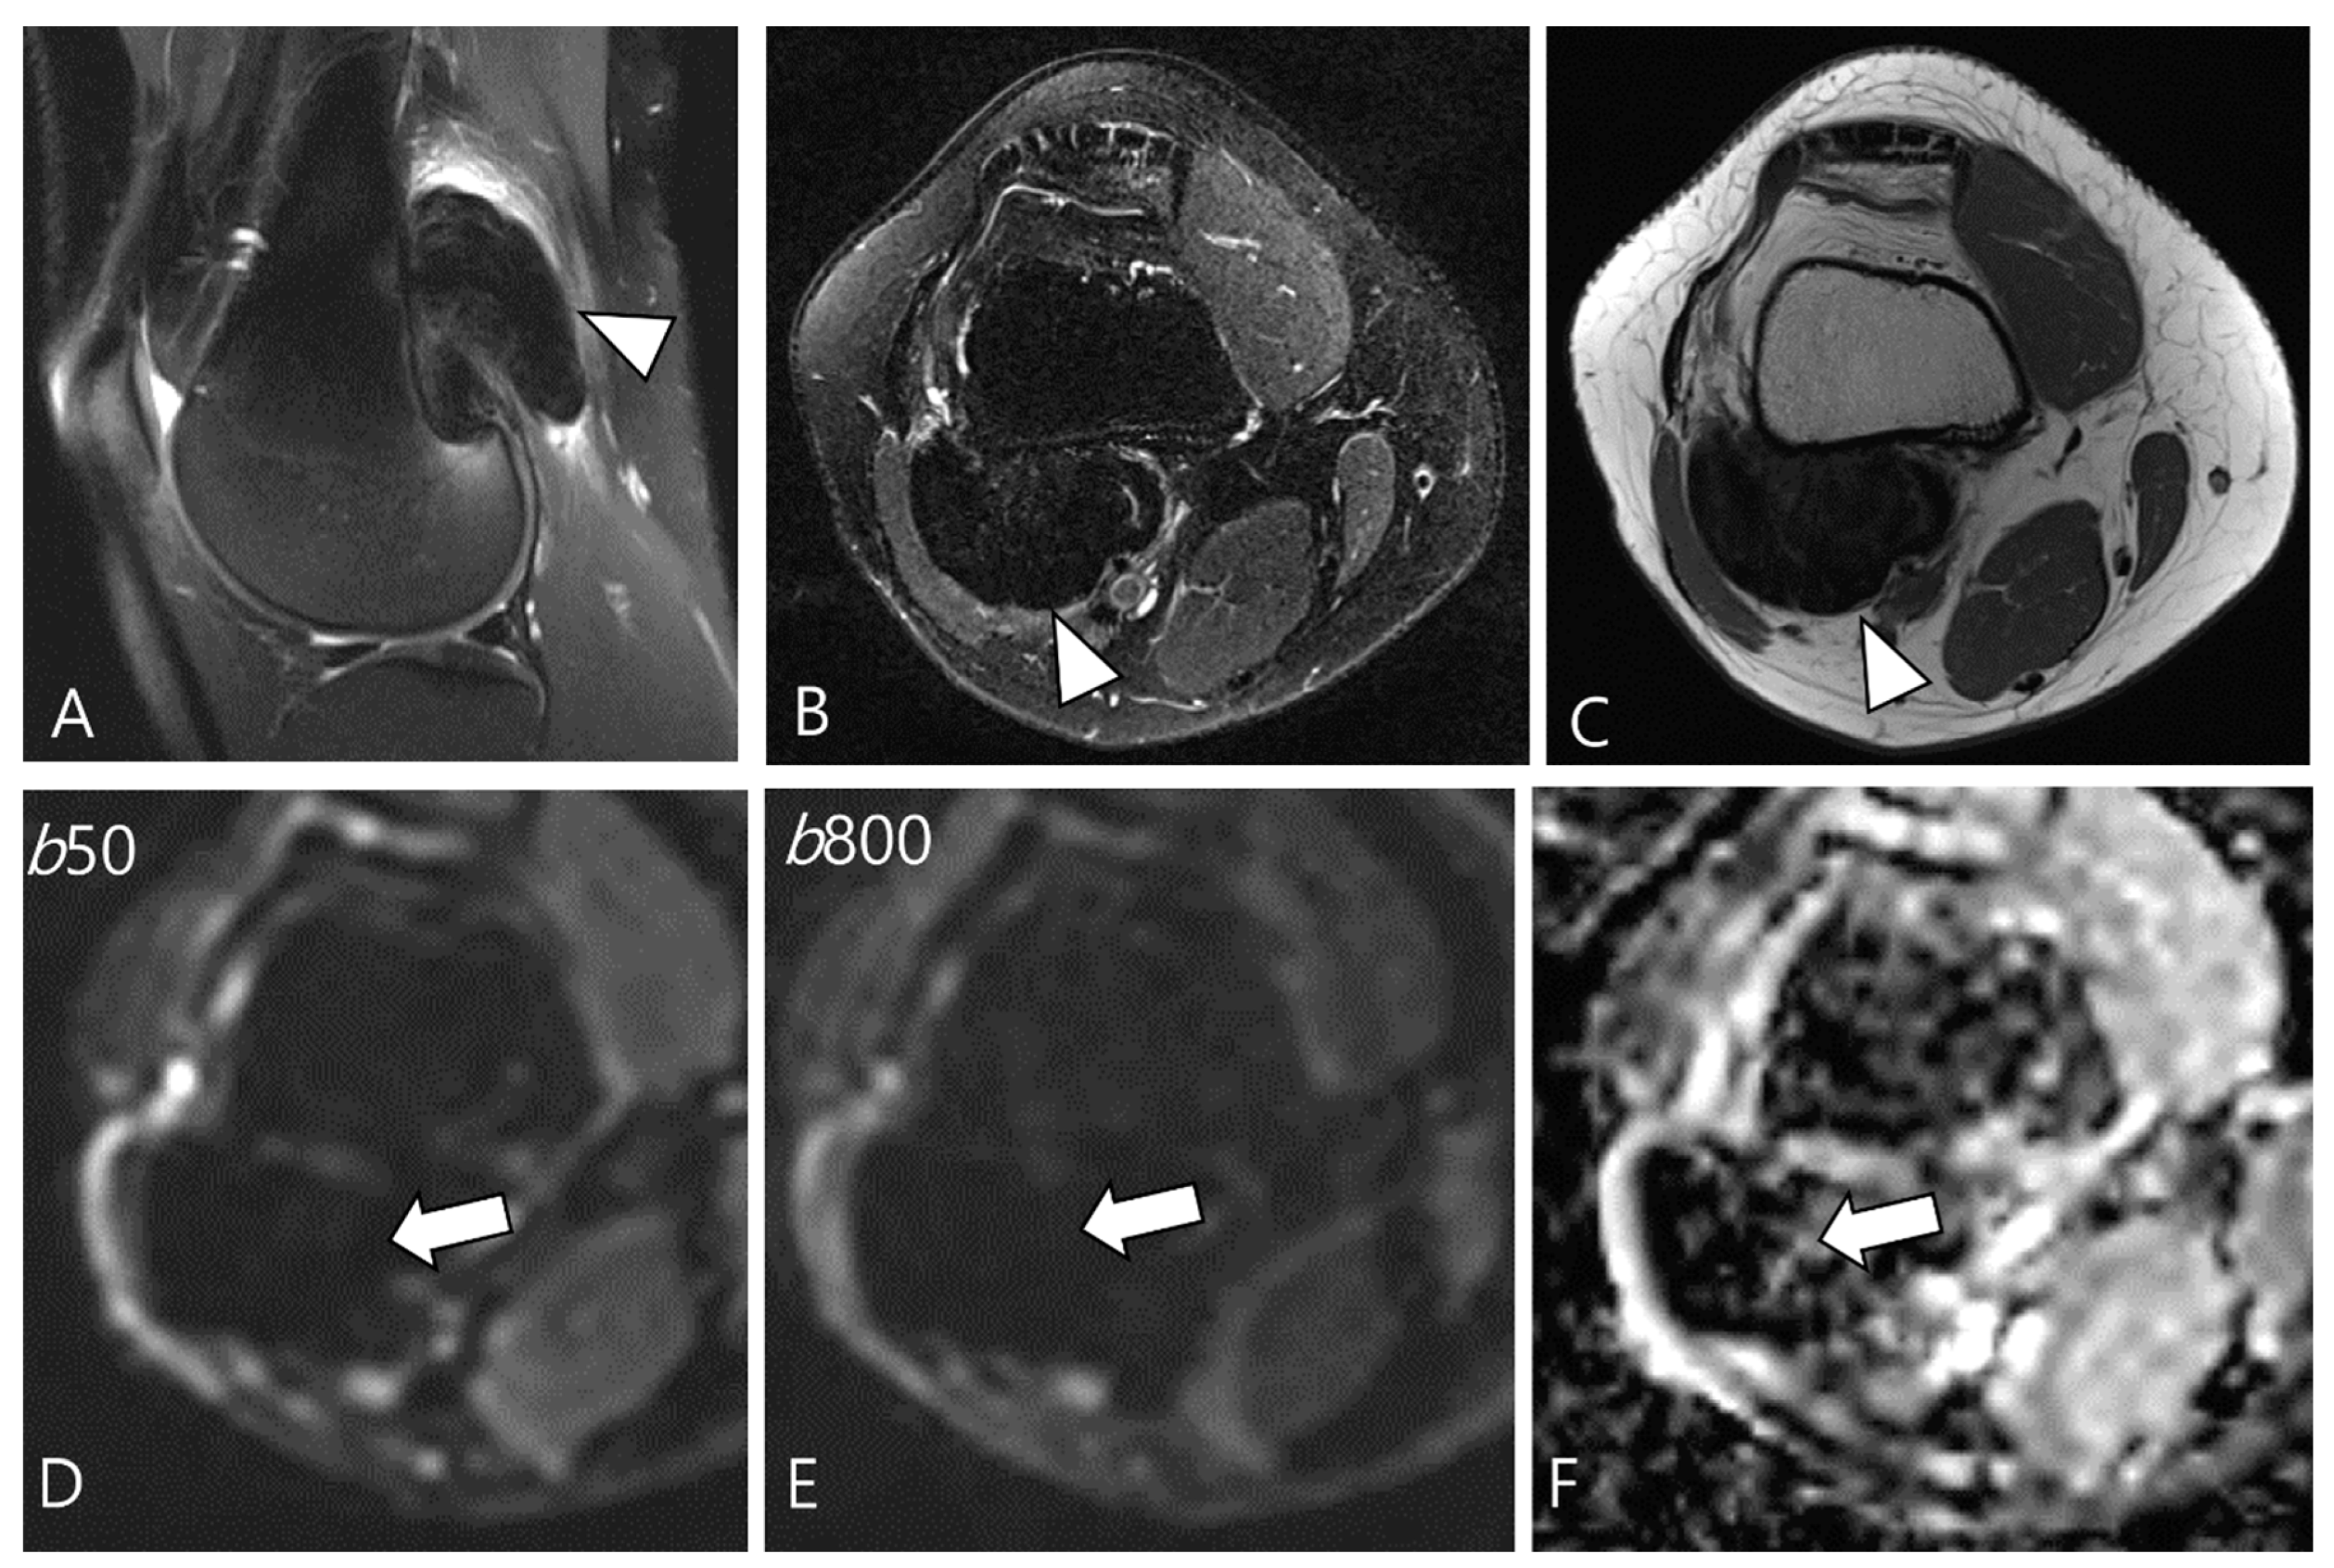

Ashikyan et al. [27] conducted a study on DWI encompassing giant cell tumor (GCT) of bone and TSGCT, which are two histologically distinct neoplasms with overlapping characteristics. Despite their different histopathological appearances, a common cell lineage is proposed, supported by a study that explored the ultrastructural cytochemical features of cells in bone, tendon sheath, and intra-articular GCTs, revealing similarities of tartrate-resistant acid phosphatase (TRAP)-positive cells in all three tumor types [40]. The study further observed that osseous GCTs and TSGCTs exhibit similar and low ADC values [27,39]. Commonly, there is a belief that malignant tumors tend to exhibit lower ADC values, while benign tumors typically display higher ADC values [41,42]. However, TSGCT may present the T2 black-out effect, resulting in a pseudo-low ADC value of less than 1.0 × 10−3 mm2/s due to the presence of hemosiderin and other blood products (Figure 7) [39,43]. Other potential reasons for the low ADC values of GCTs include the nature of the intralesional matrix or the presence of hypercellular components [27]. (TS)GCT comprises giant osteoclast-like cells interspersed with a hypercellular and vascularized stroma, and this composition can influence the lower ADC measurement (Figure 8) [44].

Figure 7.

A 29-year-old female with D-TSGCT in the distal femur. (A,B) Sagittal and axial fat-suppressed T2WIs show a low SI mass at the popliteal fossa (arrowheads). (C) Axial T1WI also shows low SI due to extensive hemosiderin deposition (arrowhead). (D,E) The mass shows low SI on low and high b-value images of DWI due to hemosiderin deposition (arrows). (F) The mass creates a pseudo-low ADC value on the ADC map (arrow), suggesting T2 black-out effect.